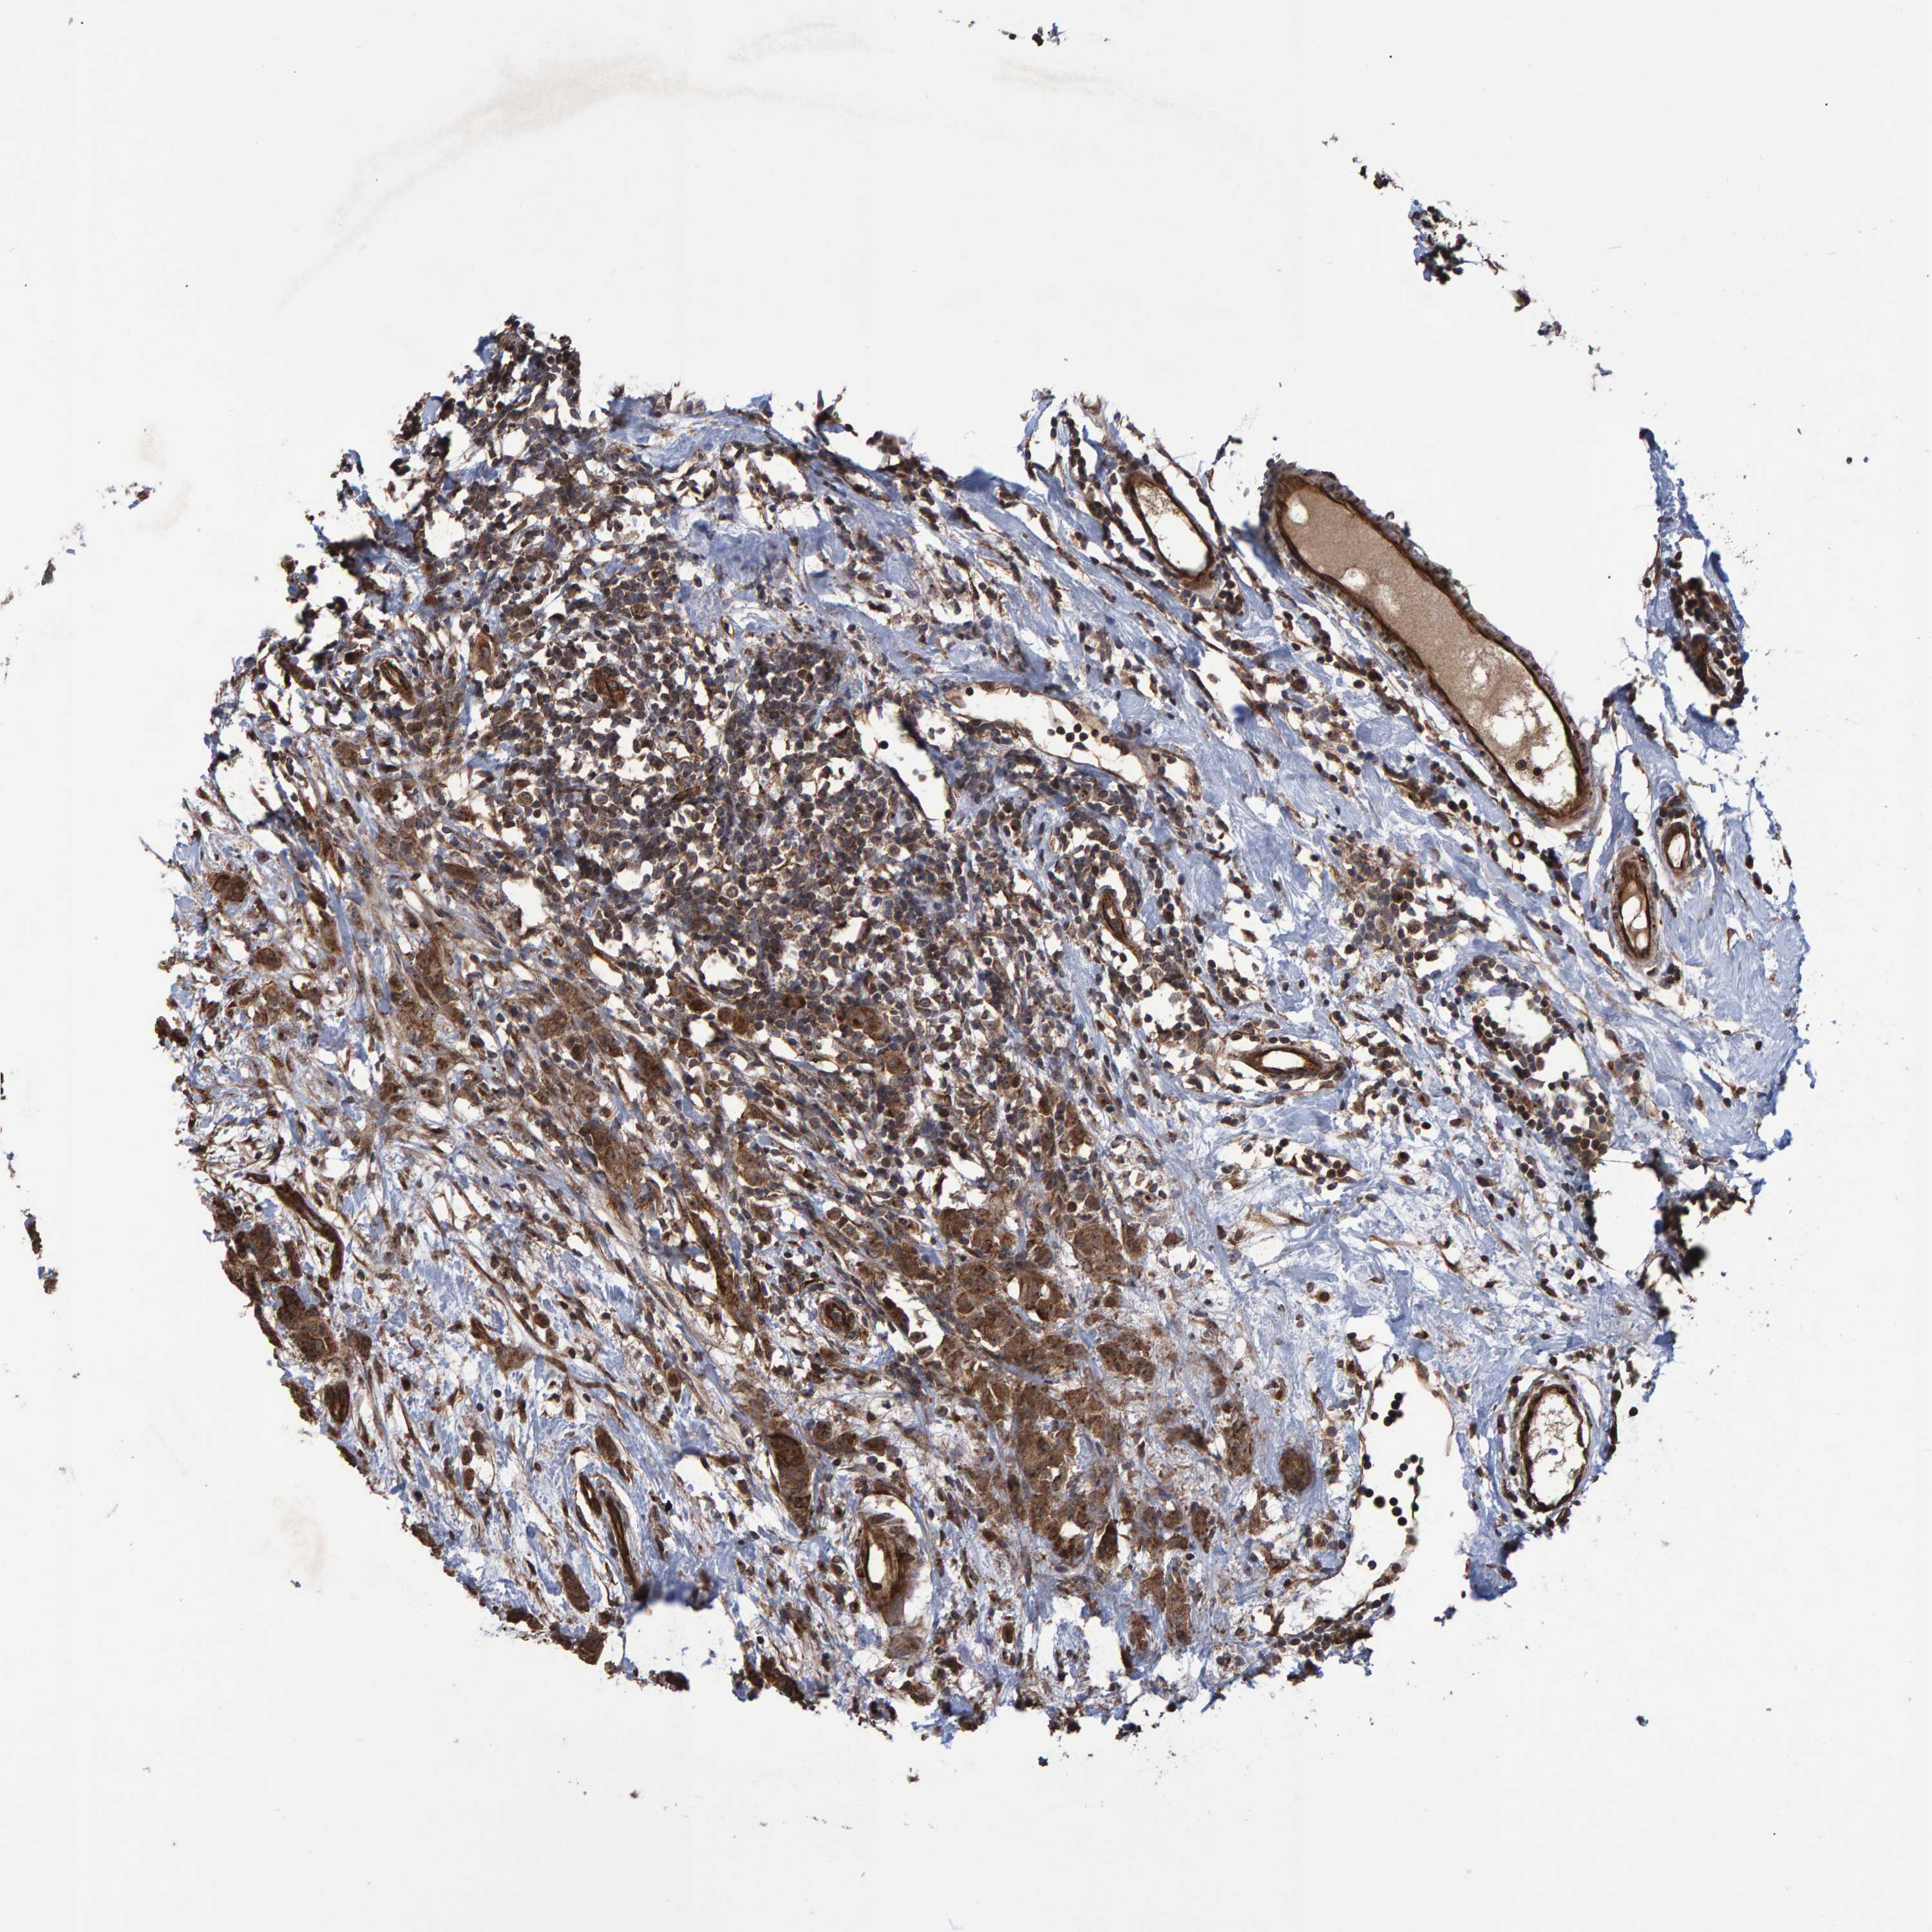

CANCER BREAST CANCER Show tissue menu

BRCA TCGA BRCA VALIDATION PROTEIN EXPRESSION